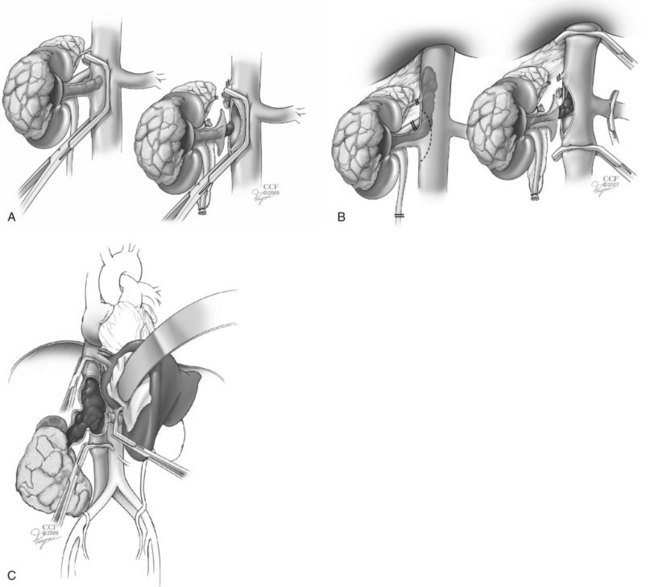

Nephron-sparing surgery for the treatment of a renal tumor was first described by Czerny in 1890 (reviewed in Herr, 2005). However, high morbidity limited its application. In 1950, Vermooten suggested that peripheral encapsulated renal neoplasms could be excised locally while leaving a margin of normal parenchyma around the tumor. Interest in PN for RCC has been stimulated by advances in renal imaging, experience with renal vascular surgery for other conditions, improved methods of preventing ischemic renal damage, growing numbers of incidentally discovered low-stage RCCs, greater appreciation of the deleterious effects of CKD, and good long-term survival in patients undergoing this form of treatment (Uzzo and Novick, 2001; Russo et al, 2008; Campbell et al, 2009; Lane et al, 2009; Novick, 2009). Nephron-sparing surgery entails complete local resection of the renal tumor while leaving the largest possible amount of normal functioning parenchyma in the involved kidney (Fig. 49–20).

Figure 49–20 Essential steps in partial nephrectomy. A, Temporary occlusion of the vascular pedicle and excision of the tumor with a rim of normal parenchyma. B, Closure of the collecting system and ligation of transected vessels. C, Capsular reconstruction.

(Reprinted with permission, Cleveland Clinic Center for Medical Art & Photography © 2007-2009. All Rights Reserved.)